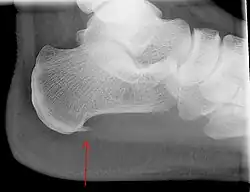

Heel bone with heel spur (red arrow)

An incidental finding associated with this condition is a heel spur, a small bony calcification on the calcaneus (heel bone), which can be found in up to 50% of those with plantar fasciitis.[6] In such cases, it is the underlying plantar fasciitis that produces the heel pain, and not the spur itself.[13] The condition is responsible for the creation of the spur, though the clinical significance of heel spurs in plantar fasciitis remains unclear.[12]

Medical imaging is not routinely needed. It is expensive and does not typically change how plantar fasciitis is managed.[15] When the diagnosis is not clinically apparent, lateral view X-rays of the ankle are the recommended imaging modality to assess for other causes of heel pain, such as stress fractures or bone spur development.[7]